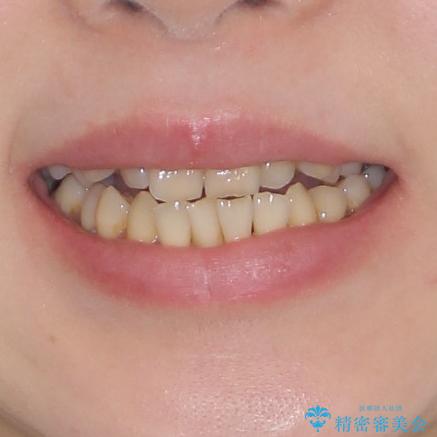

どこで咬んで良いのか分からない インビザラインでの咬み合わせの改善

- 歯列不正と、どこで咬んで良いのか分からない咬み合わせを気にして来院された患者様です。

下顎骨は左側にシフトしており、咬み合ったときには奥歯と前歯の一部しか接触していない状態でした。

骨格的な左右差は歯列矯正は改善できないため、上下歯列が全体的に接触することをゴールとしてインビザラインにて矯正治療を行うこととしました。